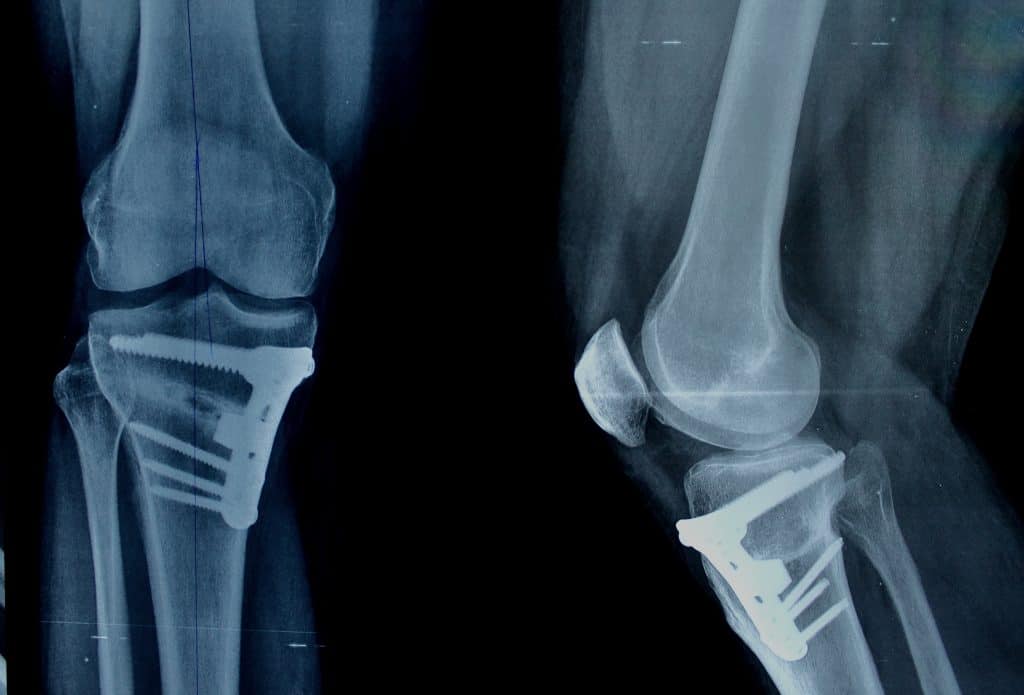

S obzirom da je osteotomija kirurški postupak kojim se režu kosti, pa se ponovno namještaju u položaj koji je normalan i prirodan, zahvat se može odvijati ovisno o kompleksnosti u općoj anesteziji, a manji zahvati u lokalnoj anesteziji. Moguće je da će biti potrebno kosti spajati pločama, vijcima, metalnim šipkama koje će pomoći u zarastanju u ispravnom položaju.